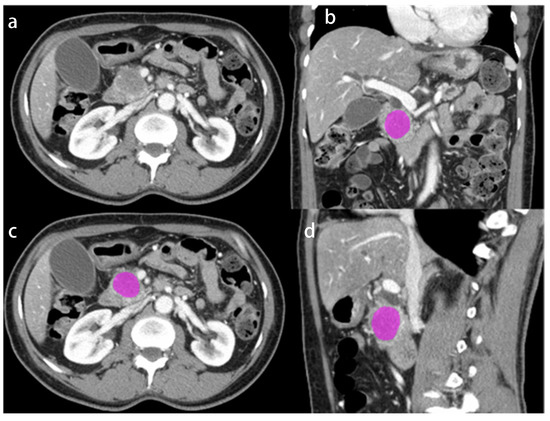

2.2. Image Segmentation, Radiomic Feature Extraction and Genomic Data